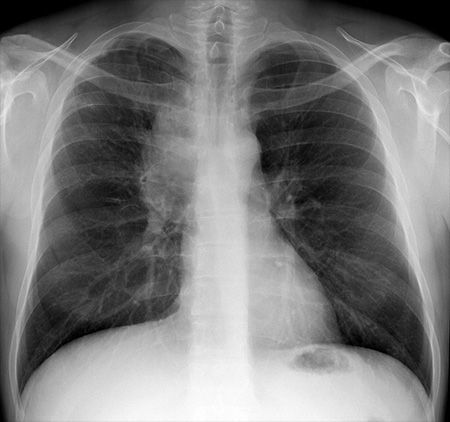

X-RAY QUIZ: Which finding is present on this image?

A: Normal X-ray image

B: Sail sign

C: Meniscus sign

D: Pneumothorax

E: Air bronchogram

Start Quiz bit.ly/36i1txn